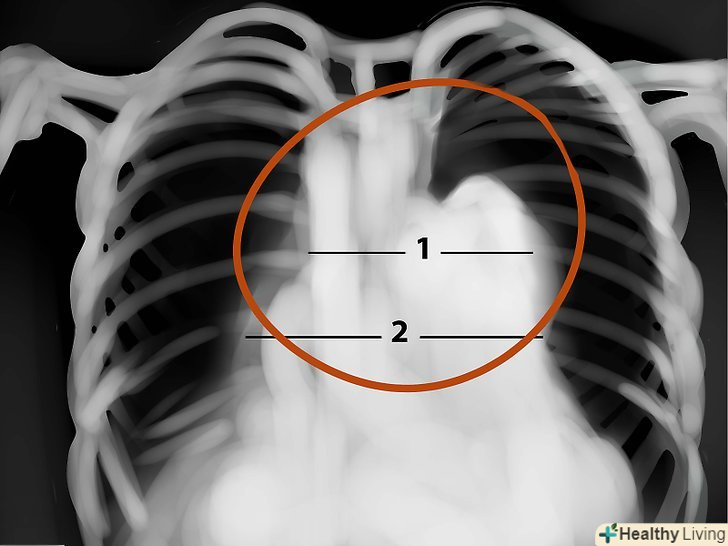

Дихальні шляхи.вони повинні бути вільні і нічим не заблокованими. Зверніть увагу на Кіль трахеї - то місце, де трахея розділяється до опускається далі, до легких.

Коріння легенів. зверніть увагу на ці області і подивіться, чи немає там якихось вузлів, силуетів і т.д. на фронтальному вигляді більшість тіней в області коренів-це ліва і права легеневі артерії. Ліва завжди вище правої. Пошукайте окальциневшіе лімфатичні вузли в області коренів-це можуть бути сліди туберкульозу.